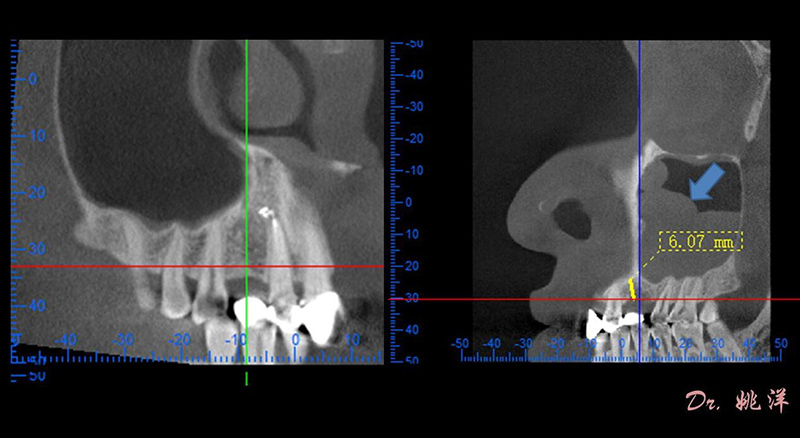

觀察患者CT,可看出患者有上頜竇粘膜囊腫,粘膜囊腫為竇內(nèi)腺體阻塞所致,視情況可有手術(shù)摘除和不予處理兩種方法,此次患者拒絕手術(shù)摘除,故需規(guī)避上頜竇位置。

根據(jù)患者CT顯示,使用種植導(dǎo)航軟件設(shè)術(shù)前手術(shù)方案??紤]到患者拒絕手術(shù)摘除上頜竇囊腫等因素,此次手術(shù)選用了Straumann骨水平4.10*8.0mm的植體,植體末端位點(diǎn)設(shè)計(jì)距上頜竇底壁2mm處的同時(shí)兼顧種植方向和修復(fù)間隙,來(lái)達(dá)到理想的效果。

從術(shù)后CBCT顯示可以看出,手術(shù)操作中完美地避開(kāi)上頜竇底,并兼顧了正確的種植方向和修復(fù)間隙